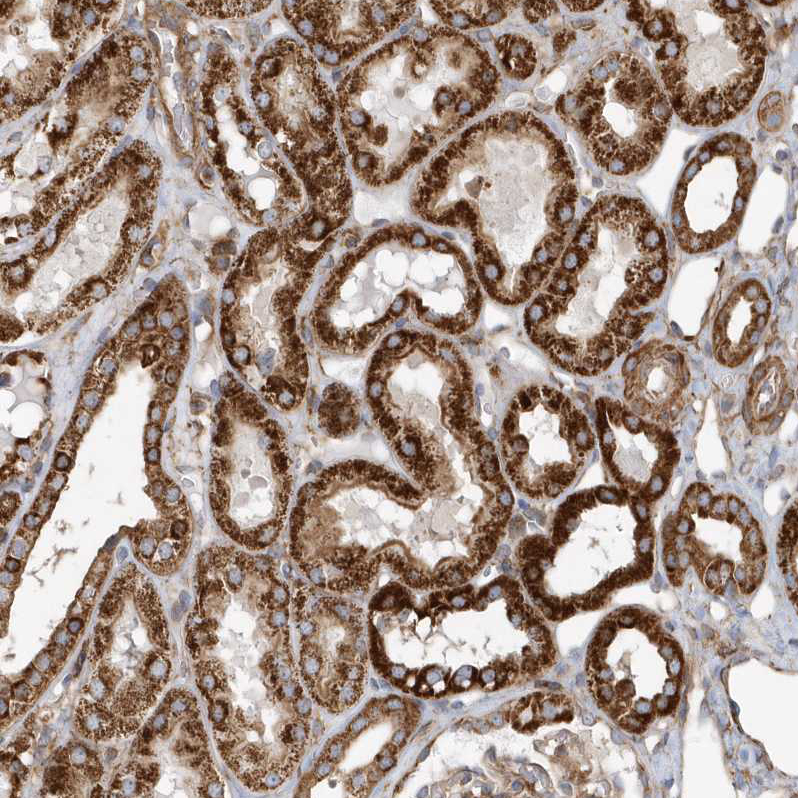

Immunohistochemical staining of human gastrointestinal, kidney, liver and pancreas using Anti-MUT antibody HPA035971 (A) shows similar protein distribution across tissues to independent antibody HPA035972 (B).